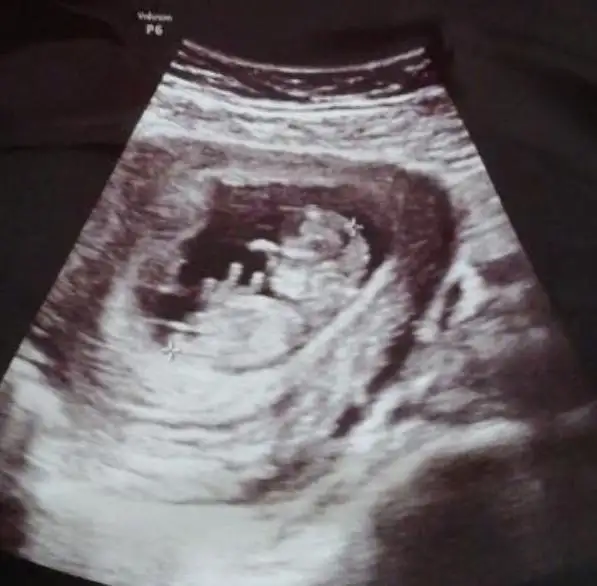

Emin konuştu ise nettir artık15. Haftada sizce net midir artık değişme ihtimali olabilir mi? Doktor çok net konuştu ama....?